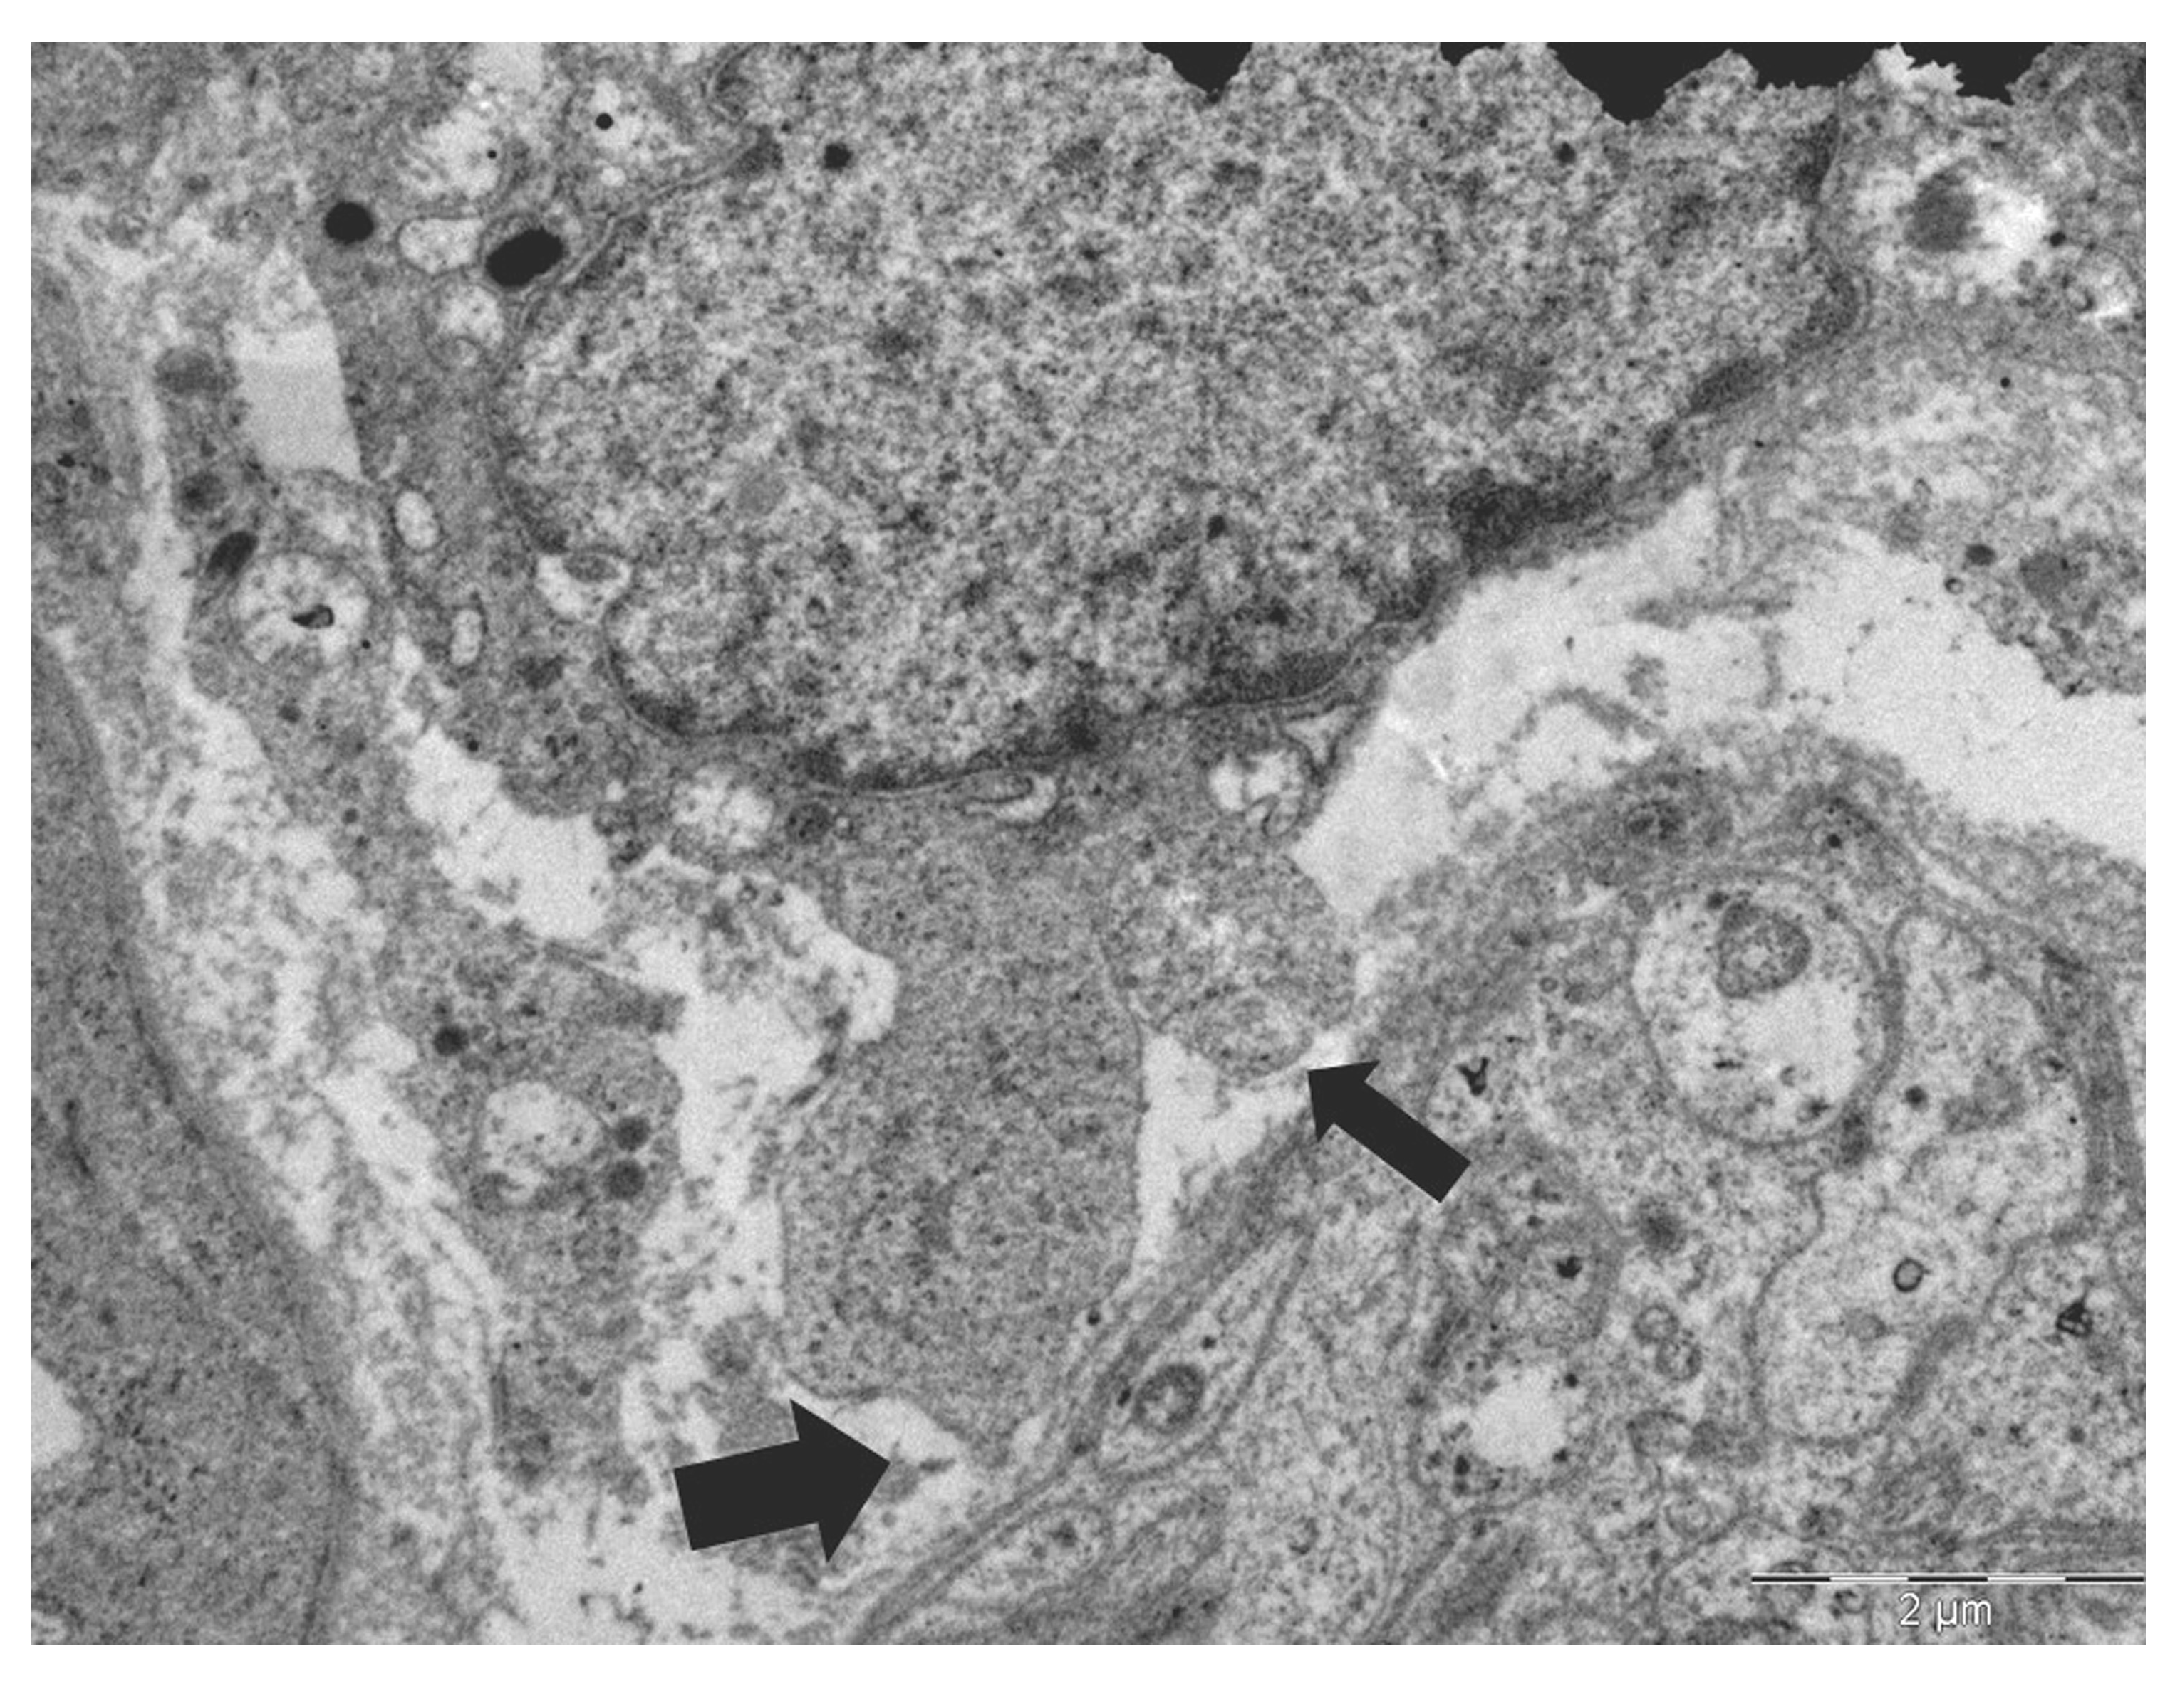

Ultrastructural Features of Amoeboid Tumor Cell–Unmyelinated Nerve Fiber Interactions in Early Gastric Cancer: A Case Report Within the Context of Cancer Neuroscience

- Marcadis, A.R.; Kao, E.; Wang, Q.; Chen, C.H.; Gusain, L.; Powers, A.; Bakst, R.L.; Deborde, S.; Wong, R.J. Rapid cancer cell perineural invasion utilizes amoeboid migration. Proc. Natl. Acad. Sci. USA 2023, 120, e2210735120. [Google Scholar]